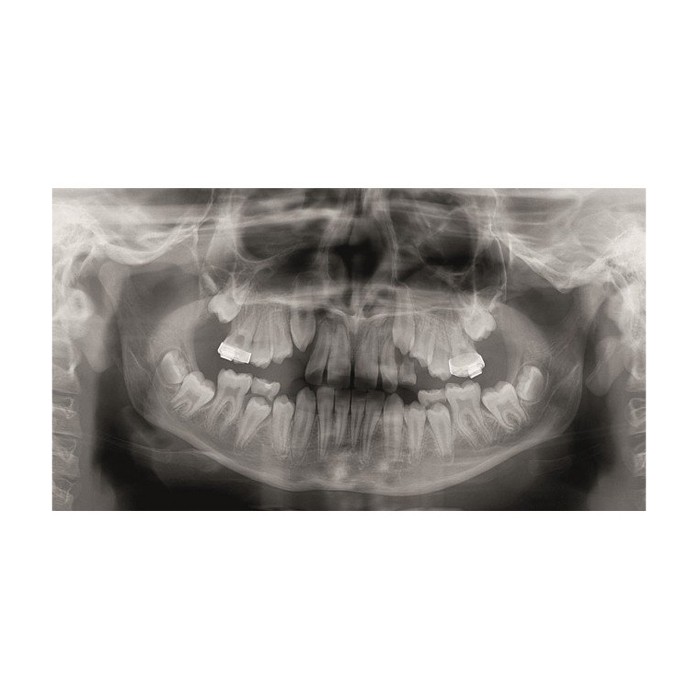

Цифровой панорамный томограф Gendex Pan eXam Plus 2D — это современное и надежное решение для оснащения стоматологической клиники или кабинета. Аппарат предназначен для получения высококачественных двухмерных панорамных снимков зубных рядов, что является основой для планирования лечения, имплантации, ортодонтической коррекции и оценки общего состояния зубочелюстной системы.

Качество изображений и диагностические возможности

Качество снимка — главный критерий выбора диагностического оборудования.

- Высокое разрешение и детализация: Цифровой датчик обеспечивает четкие и контрастные изображения с отличной визуализацией костной структуры, корней зубов, состояния пародонта и нижнечелюстного канала.

- Широкий набор программ сканирования: Аппарат поддерживает различные режимы съемки, адаптированные под конкретные клинические задачи: стандартная панорама, панорама детей, съемка височно-нижнечелюстных суставов (ВНЧС), синус-сканирование и другие.

- Мощное программное обеспечение: В комплекте поставляется интуитивное ПО для управления съемкой, обработки и анализа изображений. Возможности включают в себя масштабирование, регулировку контрастности и яркости, проведение измерений, что облегчает постановку диагноза и консультацию с пациентом.